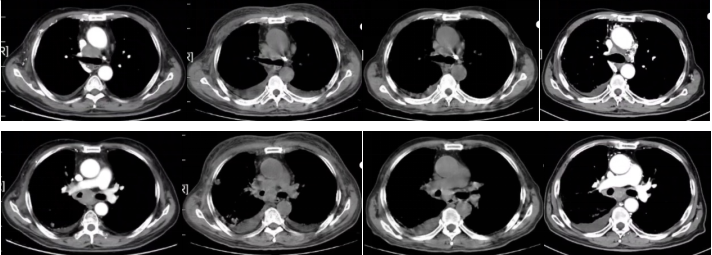

2022-07-20胸部平扫+增强CT:恶性肿瘤维持性化学治疗后,较2022-3-31胸部CT旧片,右肺中叶占位(5.3×8.1cm)增大;双肺转移结节(较大者位于右肺上叶,长径约2.2cm)增大、增多;纵隔及右肺门淋巴结增大,上腔静脉受侵;右侧胸腔积液增多;余未见显著变化。附见,胰尾占位,腹膜后淋巴结增大,转移可能。

图2

疗效评价:PD。